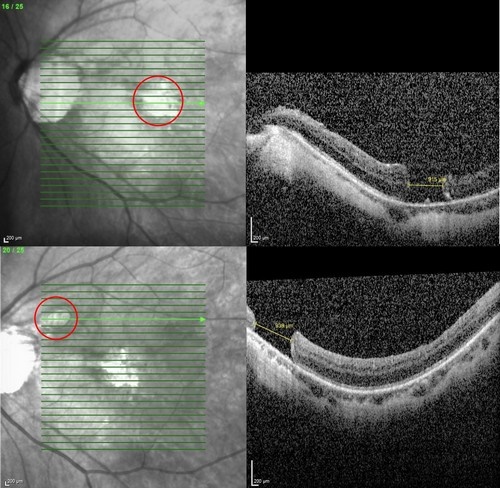

何明山主任在仔細檢查發現,張女士左眼同時有兩處大型黃斑部裂孔,分別為915與939微米,屬於少見的雙裂孔個案。何明山主任表示,得知張女士從過去一例成功治癒巨大黃斑部裂孔的報導中抱著希望,專程來到花蓮就診,針對此特殊情況,何明山主任採用創新雙重療法,以羊膜移植修補破洞,並輔以自體高濃度血小板血漿(platelet-rich plasma, PRP)注射,促進組織修復與裂孔癒合。

左圖:張女士左眼同時有兩處大型黃斑部裂孔,分別為915與939微米,屬於少見的雙裂孔個案。

右圖:張女士經羊膜及PRP雙重療法後,兩處大型黃斑部裂孔順利癒合,張女士一解長期以來的困擾,開心表示終於能回歸日常生活。